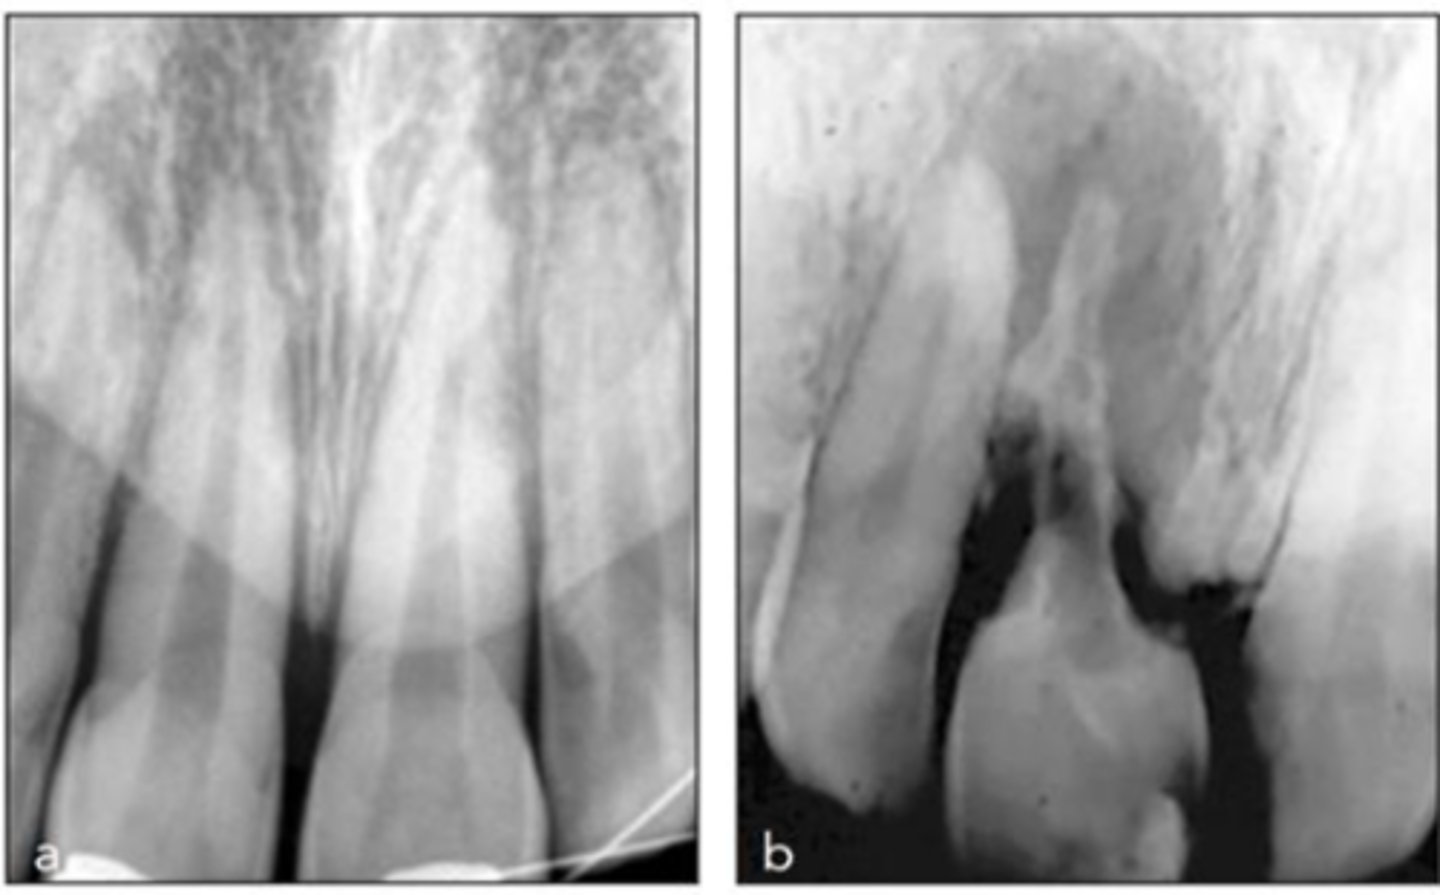

External Replacement Resorption/Ankylosis

Which type of resorption?

- Fusion of cementum or dentin with alveolar bone

Which type of resorption>

- Damage to PDL ⇒ stimulus for surrounding bone to activate osteoclasts and begin resorbing cementum/dentin and replacing it with bone tissue

- Almost always due to trauma (luxation, intrustion, avulsion, replantation)

ID the type of resorption:

RADIOGRAPHIC

- Absence of lamina dura/PDL

- Bone trabeculation occupying previous root surface

- CBCT is often helpful to assess the full extent

Patient presents with these radiographic findings. What is the most likely diagnosis?

- Absence of lamina dura/PDL around lesion.

- Bone trabeculation occupying previous root surface.